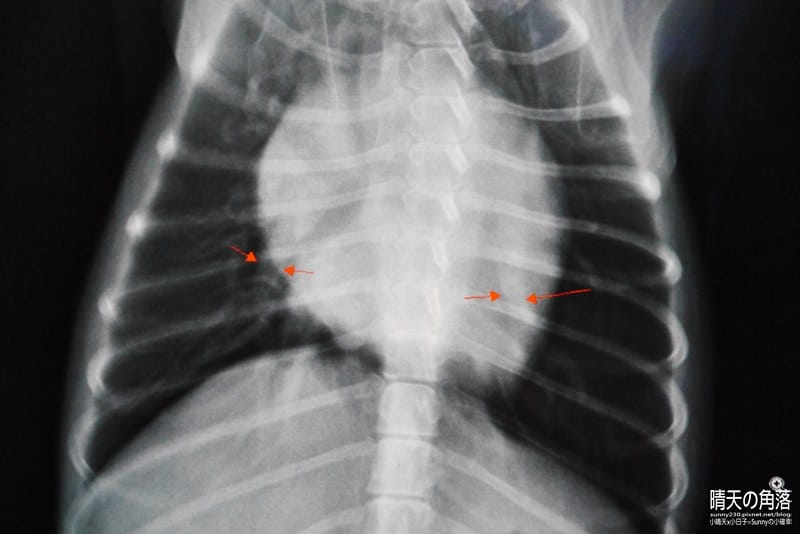

動物醫院的醫生說要做X光檢查…等,才能確診

結果診斷出來了,狗醫生卻說不是噎到也不是感冒…

是「狗狗的心臟病」!

經醫生說明了解,點點有心臟肥大、二尖瓣逆流合併肺水腫、心雜音…等的情形